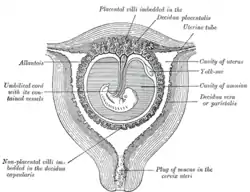

Sectional plan of the gravid uterus in the third and fourth month | |

The part of the decidua that interacts with the trophoblast is the decidua basalis (also called decidua placentalis), while the decidua capsularis grows over the embryo on the luminal side, enclosing it into the endometrium. The remainder of the decidua is termed the decidua parietalis or decidua vera, and it will fuse with the decidua capsularis by the fourth month of gestation.